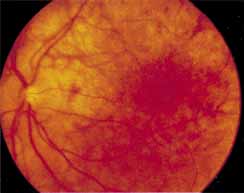

During the early stage of the dystrophy, when patients demonstrate a slight-to-moderate decrease in visual acuity and minimal color defects, there are minor or no visible fundus abnormalities. At most, the foveal reflex may be absent and there may be some increased granularity of the retinal pigment epithelium in the macula. Later, there is a decrease of visual acuity to the 20/400 range, oval atrophy of the macular retinal pigment epithelium (“beaten bronze” atrophy), and associated choroidal atrophy (Fig. 3). A characteristic bull's-eye maculopathy, similar to that seen in patients with chloroquine retinopathy, may also be seen.90 Photophobia, occasional nyctalopia, incomplete-to-complete color defects, and a central scotoma are often present. The symmetry of the process in both eyes is remarkable.